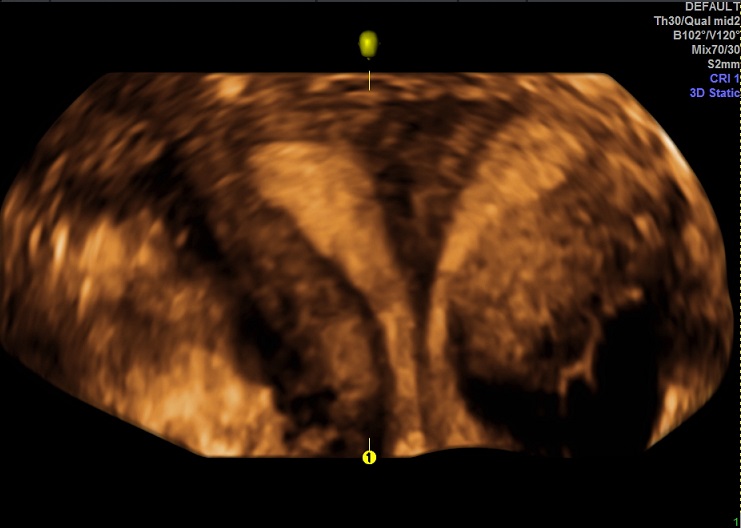

女性,25岁,原发性不孕2年,有子宫畸形病史,畸形类型不详。常规二维超声子宫横径增宽,宫底部横切面内膜不连续,动态扫查似显示为Y型。宫腔三维显示:两侧宫角分开成Y型,内膜凹陷达到宫颈内口。诊断:完全中隔子宫。